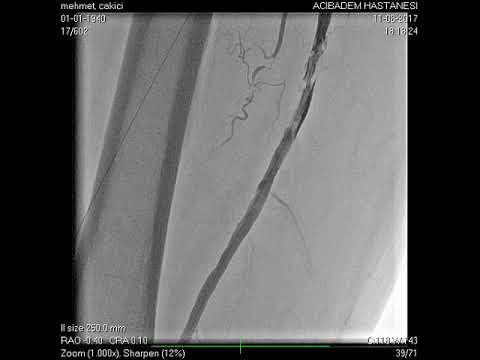

Anjiyografik İşlemler